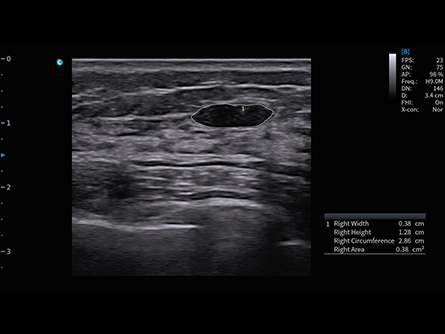

Experimenta la excelencia en radiología con los equipos de ultrasonido de CHISON. Nuestros dispositivos de alto rendimiento ofrecen imágenes de precisión y características avanzadas, satisfaciendo las demandas de los radiólogos de todo el mundo. Desde la visualización clara de tejidos blandos hasta escaneos rápidos, nuestras máquinas optimizan el flujo de trabajo, garantizando la precisión diagnóstica. Explora nuestras soluciones de ultrasonido de radiología mejor valoradas para una atención superior al paciente y satisface las necesidades de tus pacientes con confianza.

Dedicated Features